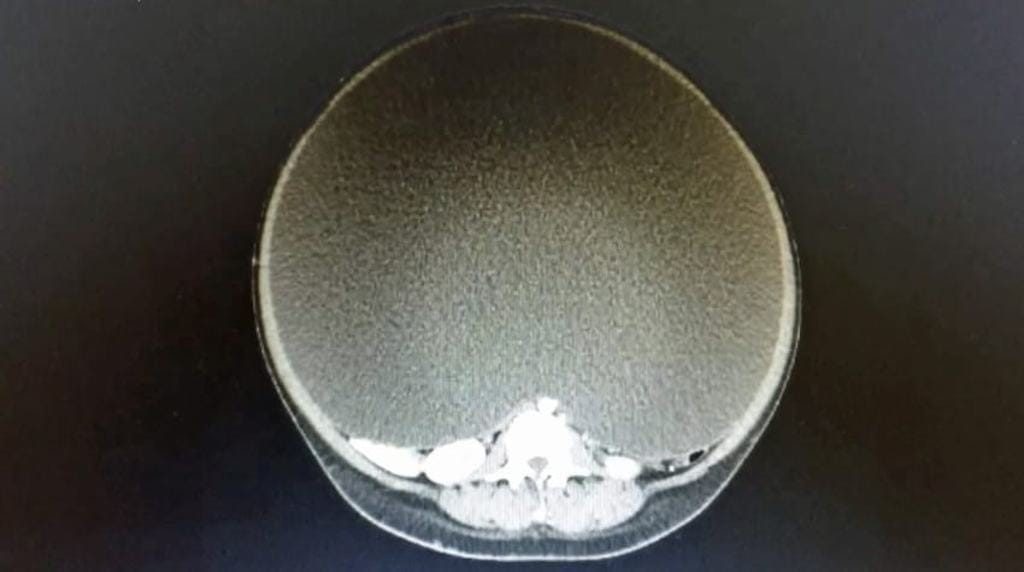

Com apenas 24 anos, parecia que ela estava grávida de 10 crianças, mas na verdade tudo aquilo era simplesmente um cisto em seu ovário pesando aproximadamente 30 quilos, esmagando seus órgãos internos.

Porém, a ideia de retirá-lo surgiu por medo de que a drenagem causasse ainda mais problemas caso o cisto fosse cancerígeno. Felizmente, a cirurgia foi mais do que necessária e ela teve 95% de seu abdômen removido, fazendo com que tarefas básicas do dia a dia da mulher se tornassem definitivamente um desafio. No total, o cisto media 50 cm de um lado e 154 ao redor.

“Quando eu a conheci, ela poderia dar apenas alguns passos antes de ficar agitada e sentir dificuldade para respirar, já que o cisto estava esmagando seus pulmões,” disse o Dr. Hanson ao Daily Mail. ”Se não tivéssemos operado, chegaria a um ponto onde ela não conseguiria andar e estaria totalmente desidratada, sem conseguir comer. É difícil dizer quanto tempo ela teria vivido, mas não teria nenhuma qualidade de vida.”